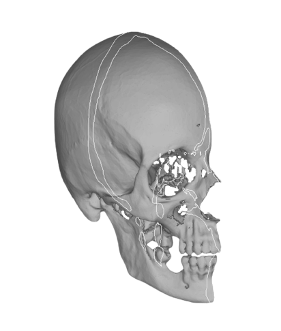

Анатомические изображения срединной сагиттальной линии черепа